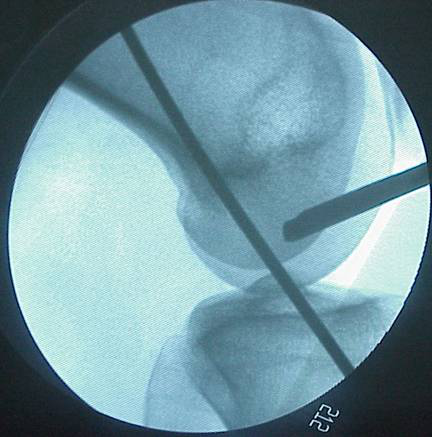

1.準確定位,建立骨隧道。

關節(jié)鏡手術專用器械

2.體位和麻醉:仰臥,小腿下垂,膝關節(jié)呈90度。腰麻或連續(xù)硬膜外麻醉

1)關節(jié)鏡檢查

2)清理關節(jié)腔:修整半月板、滑膜、軟骨

3)斷裂ACL的處理:保留ACL雙側斷端, 有連續(xù)的韌帶不予切斷,顯露ACL與 PCL之間的股骨外髁內(nèi)側窩頂后壁下緣。

4)在脛骨結節(jié)內(nèi)3-4厘米、下1.5厘米處切口切取半腱肌、股薄肌,縫合兩端,測試肌腱的直徑,以確定轉頭的直徑。

脛骨點選取

股骨點